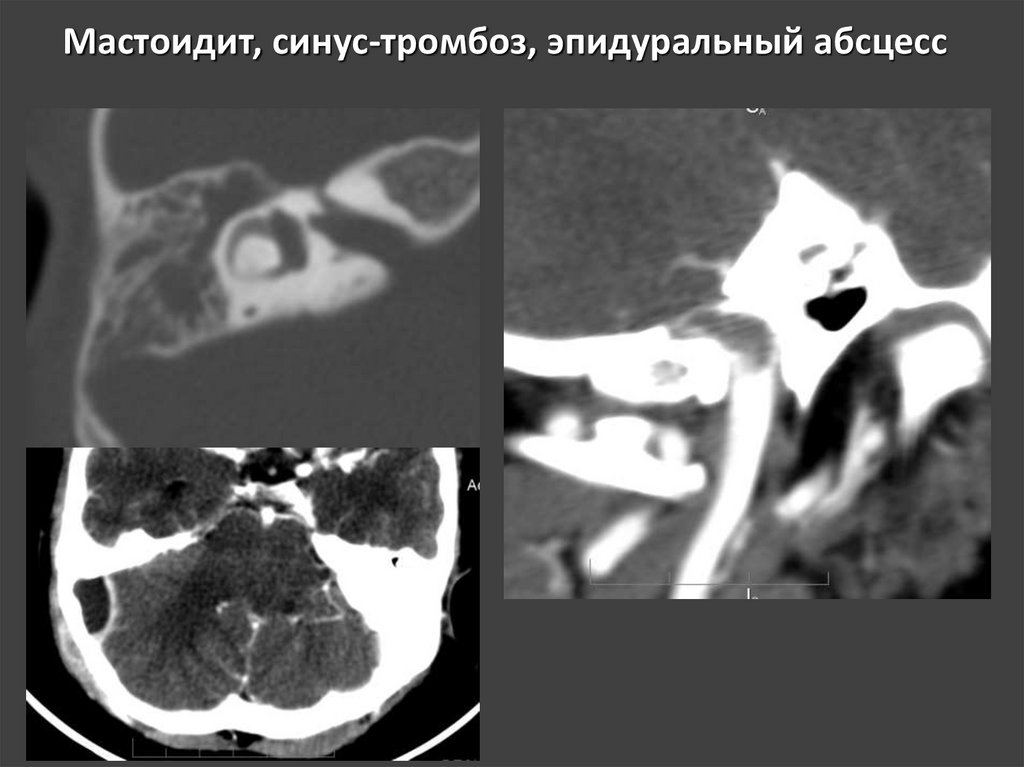

Гломусная опухоль югуло-тимпанической локализации

34. Мастоидит, синус-тромбоз, эпидуральный абсцесс